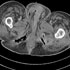

Forensic radiology represents the intersection of diagnostic imaging and legal medicine, playing an increasingly vital role in modern medicolegal investigations.